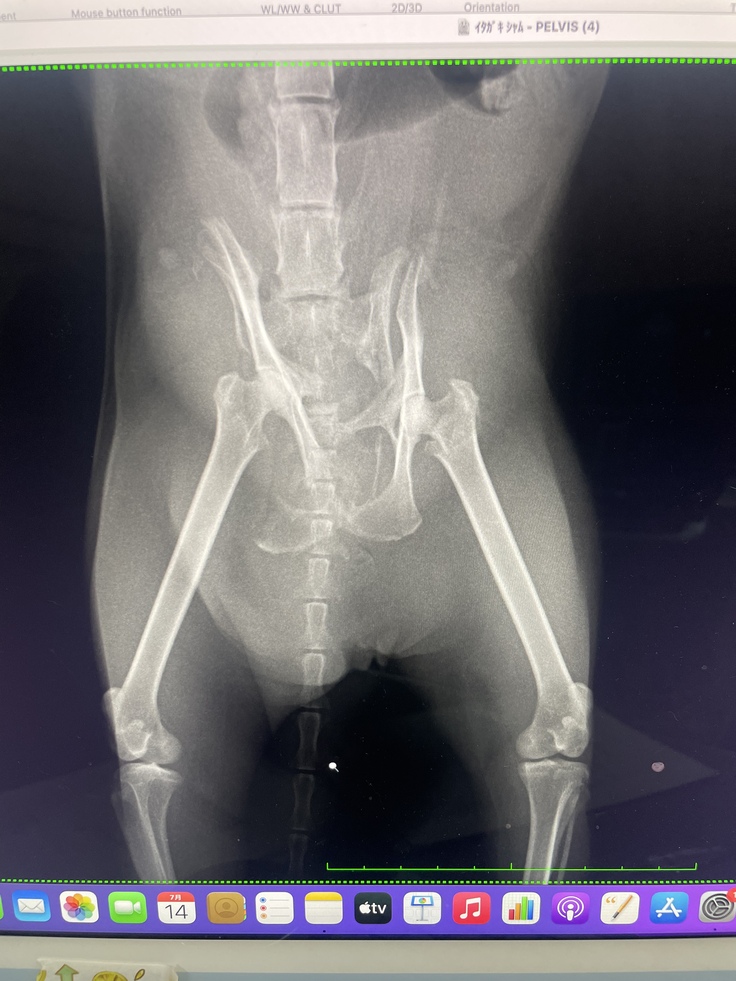

↓レントゲン骨盤骨折と診断

(左腸骨、右腸骨、坐骨骨折)